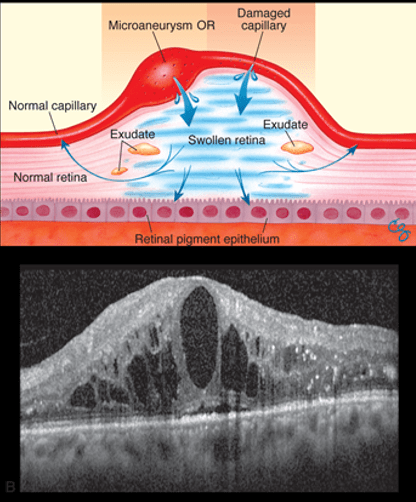

What is macular edema?

- It is the build-up of fluid in the macula, an area in the center of the retina.

- The macula is the part of the retina responsible for sharp, straight-ahead vision.

- Fluid build-up causes the macula to swell and thicken, which distorts vision.

What causes macular edema?

- In diabetes, high blood sugar affects the small blood vessels or microcirculation

- The retinal blood vessels are some of the smallest blood vessels are often affected first in diabetes.

- Abnormal leakage and accumulation of fluid in the macula occurs from these damaged blood retinal vessels.